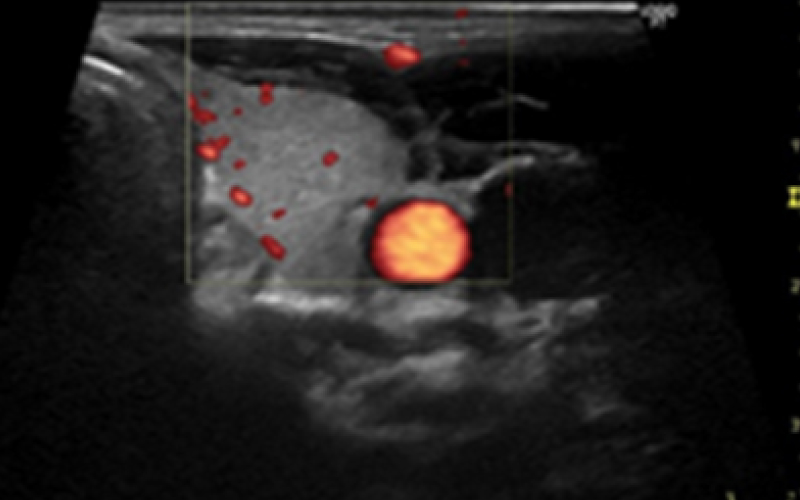

超音波検査

頸動脈

脳梗塞・心筋梗塞・心臓弁膜症などの疾患において、頸部(首)の血管の動脈硬化や血液の流れ具合を超音波で調べる検査です。